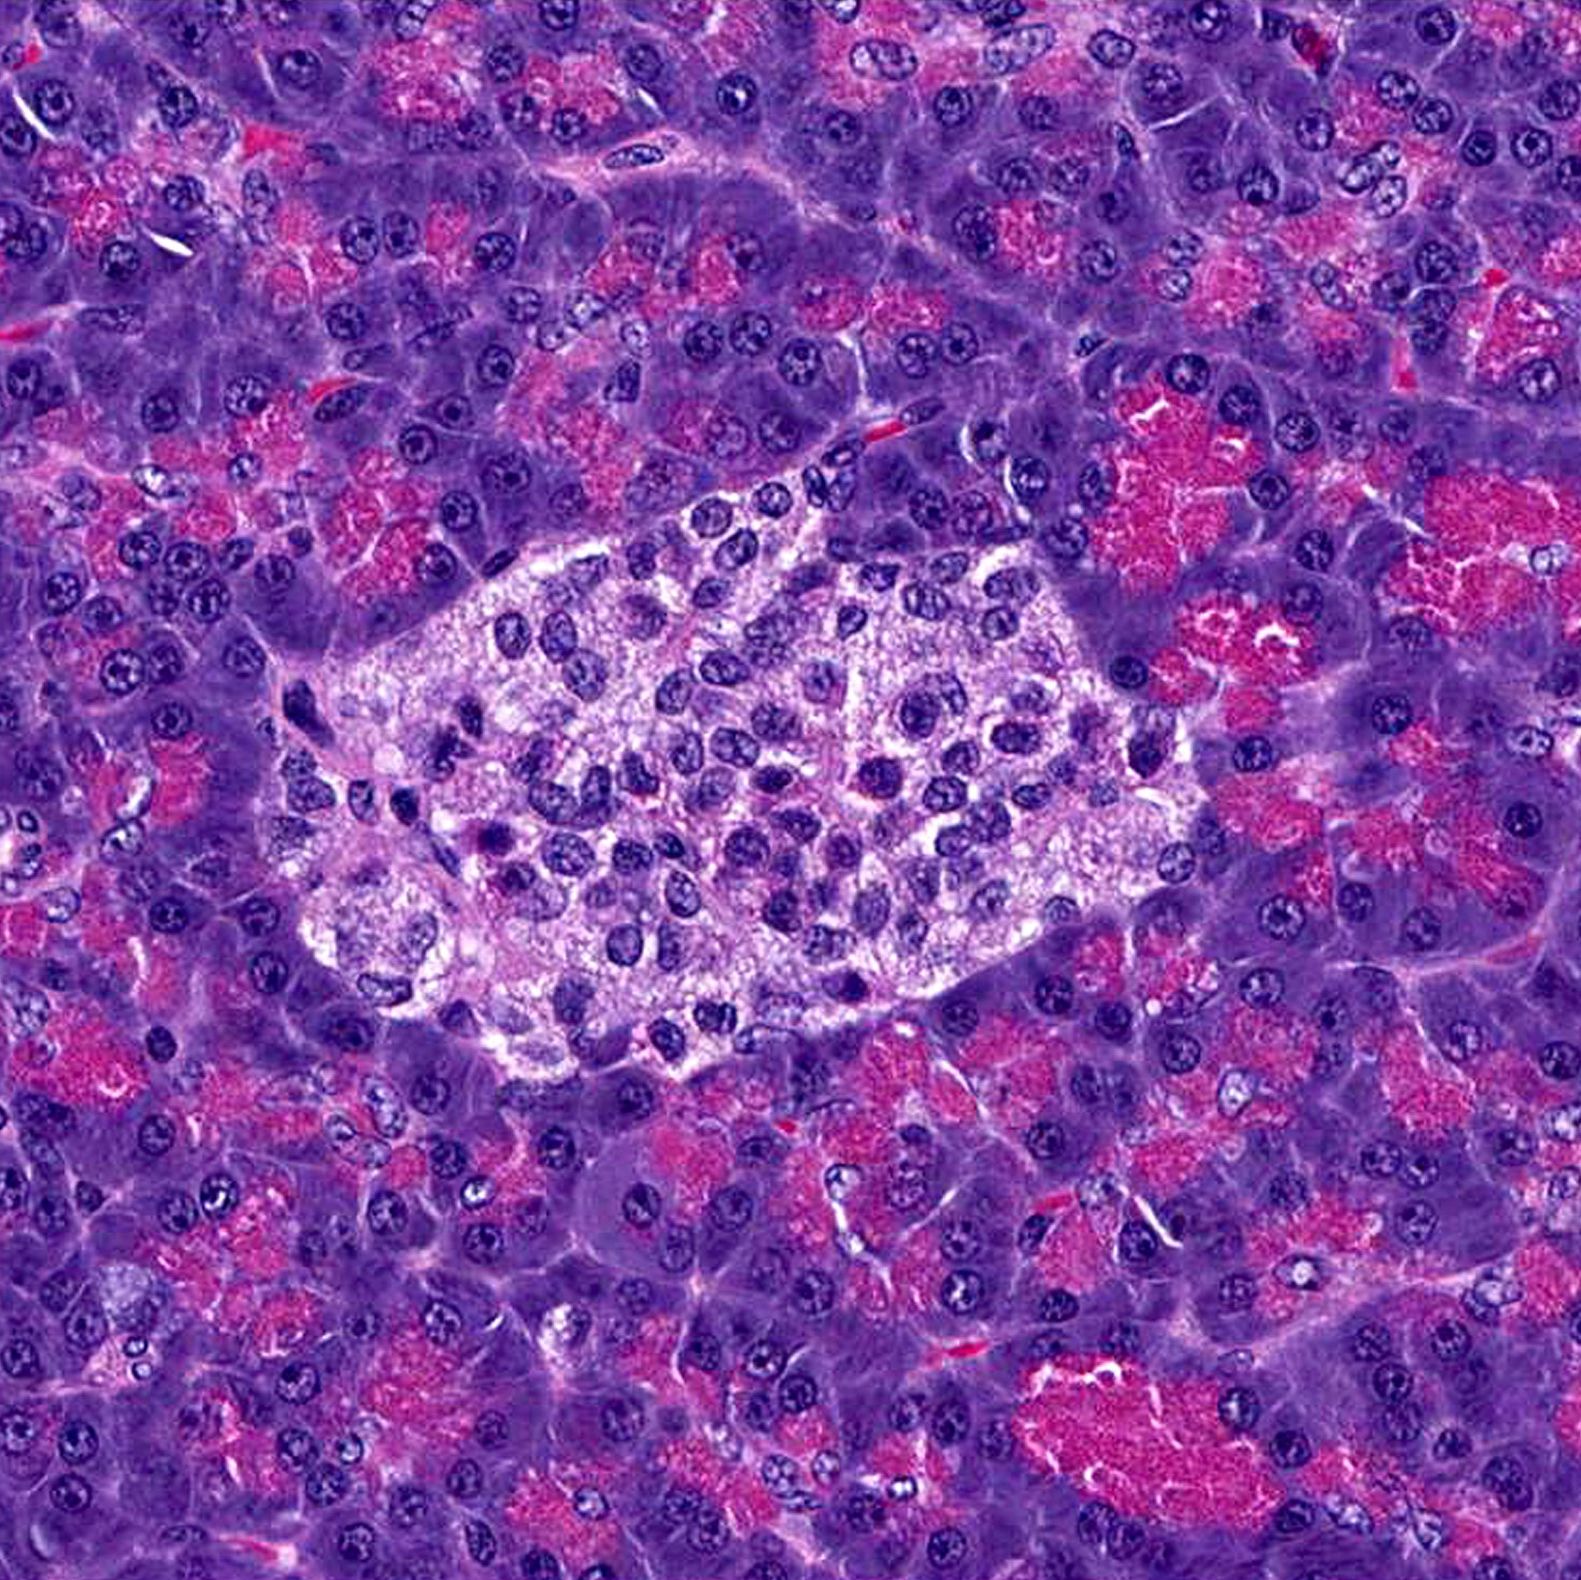

Dank eines einzigartigen interdisziplinären Data-Science-Programms der Helmholtz-Gemeinschaft kann sie beides verbinden und modernste Methoden der Data-Science nutzen, um den Verlauf von Diabetes auf Zellebene besser zu verstehen. Als Doktorandin an der Munich School for Data Science der Helmholtz Information and Data Science Academy arbeitet Hrovatin an einem besseren Verständnis der Betazellen, der Insulinfabriken des Körpers. Betazellen befinden sich in der Bauchspeicheldrüse und reagieren auf steigende Glukose-Werte im Blutkreislauf, den Blutzuckerspiegel, mit der Produktion des Hormons Insulin. Dieses wiederum signalisiert den Muskelzellen, Blutzucker aufzunehmen und für die spätere Nutzung zu speichern.

Das Labor des Instituts für Computational Biology des Helmholtz-Zentrums München, an dem sie arbeitet, befasst sich hauptsächlich mit Einzelzell-Sequenzierung, einer Technik der Datenanalyse, mit der Biologen Zelleigenschaften bei Mäusen mit Diabetes direkt untersuchen können. Trotz des riesigen Potenzials findet die Forschung auf mikroskopischer Ebene statt: Hrovatins Kollegen entnehmen den Nagern Zellen der Bauchspeicheldrüse und isolieren aus dem Organgewebe einzelne Zellen, deren Eigenschaften und Reaktion auf Behandlungen und Stress sie dann untersuchen.

Die Betazellen werden in einem winzigen Röhrchen aufgereiht, einzeln in Öltröpfchen eingeschlossen und jeweils mit einer eindeutigen Kennung markiert. Ein Datensatz kann auf nur 10.000 Zellen basieren, eine Menge, die mit bloßem Auge kaum zu sehen ist.